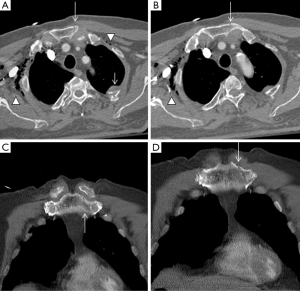

Sternoclavicular dislocation

Sternoclavicular dislocations account for fewer than 5% of all dislocations of the scapular belt. Most cases of anterior dislocation of the sternoclavicular joint do not present with any clinical symptoms. However, some patients may develop chronic anterior instability and may continue to present symptoms. In these cases, surgical treatment is indicated (27). Sternoclavicular dislocations usually occur following traumatic events. Anterior dislocation often follows motor vehicle accidents, or occurs during sporting activities. Posterior dislocation is considered less common and it is classically secondary to indirect trauma. When a force is applied to the posterolateral shoulder, the lateral portion of the clavicle is displaced anteriorly. With a taut costoclavicular ligament acting as a fulcrum, the medial clavicle is then levered behind the sternum. Direct trauma to the anteromedial portion of the clavicle is a considerably less frequent condition (28).

Nevertheless, other authors contradict previously reported results; in a study of 41 patients with sternoclavicular joint pain related to trauma, MRI found 24 subluxations (59%), which antero-posterior axis was displaced anterior in three patients (7%) and posterior in 11 patients (27%), whereas supero-inferior axis was superior in 17 patients (41%) and inferior in two (5%). The authors explained this discrepancy based on their patient population, consisted of patients with more delayed and chronic symptoms (29). Dislocation of the sternoclavicular joint should always be considered in a trauma patient with pain, swelling, or deformity over the medial clavicle. Because of the potential for serious complications with a posterior dislocation, rapid diagnosis is essential. In practice, this will usually involve a chest radiograph, one of the specialized sternoclavicular views, followed by an immediate CT examination if possible (27). In fact, posterior sternoclavicular dislocations may be subtle or not visualized on conventional radiography. Therefore, when there is a clinical suspicion for this entity, CT with intravenous contrast material administration can be used to confirm the diagnosis and evaluate for possible associated vascular injury (1).